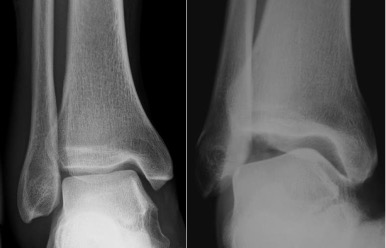

Anteroposterior view ankle (AP ankle)

Radiographic technique

Taken with the X-ray beam directed along the longitudinal axis of the foot towards the ankle, centred on a point midway between the malleoli.

Anatomical review areas

- Ankle mortise including trochlear surface of the talus, tibial plafond and malleoli

- Useful if ankle injury and avulsion fractures are suspected

- Virtually no detail of the forefoot due to superimposition

Modifications

Mortise view

- Taken with foot internally rotated 15-20°

- Projects fibula off medial tibial plafond

- Allows assessment of ankle mortise and distal tibiofibular syndesmosis

Lateral view ankle (weightbearing)

Lateral X-ray beam centred 2 cm above the inferior tip of the lateral malleolus, with the side of the foot against the image receptor.

- Distal fibula (seen through tibia)

- Posterior lip of the tibia, also known as the posterior (or third) malleolus

- Tibiotalar and subtalar joints

- Talar dome

- Facets of the subtalar joint and calcaneum